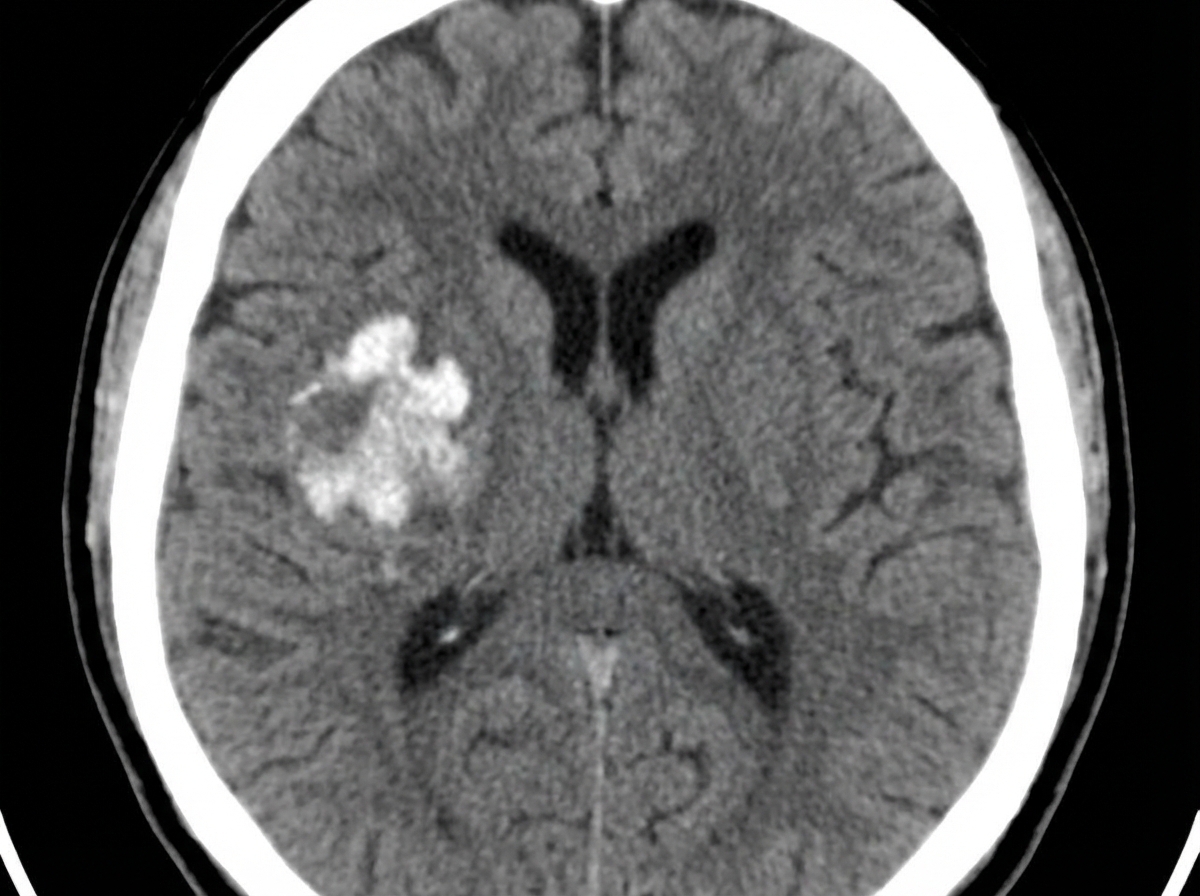

The NCCT shows the presence of which of the following?

Explanation: ***Right intra-parenchymal hemorrhage*** - **NCCT** shows a **hyperdense lesion** within the right cerebral parenchyma, indicating acute blood within brain tissue. - The hemorrhage is confined to the **brain parenchyma** rather than ventricular spaces, with characteristic **mass effect** and surrounding edema. *Left intraventricular hemorrhage* - Blood would be confined to the **ventricular system** on the left side, appearing as hyperdensity within ventricles. - **NCCT** would show blood filling the **lateral ventricles** rather than parenchymal tissue involvement. *Right intraventricular hemorrhage* - Blood would be limited to the **right ventricular system**, not extending into brain parenchyma. - Appears as **hyperdense material** within ventricles without the parenchymal mass effect seen here. *Left intra-parenchymal hemorrhage* - Would show **hyperdense lesion** in the left cerebral hemisphere, not the right side. - **Laterality** is incorrect based on the NCCT findings showing right-sided parenchymal involvement.